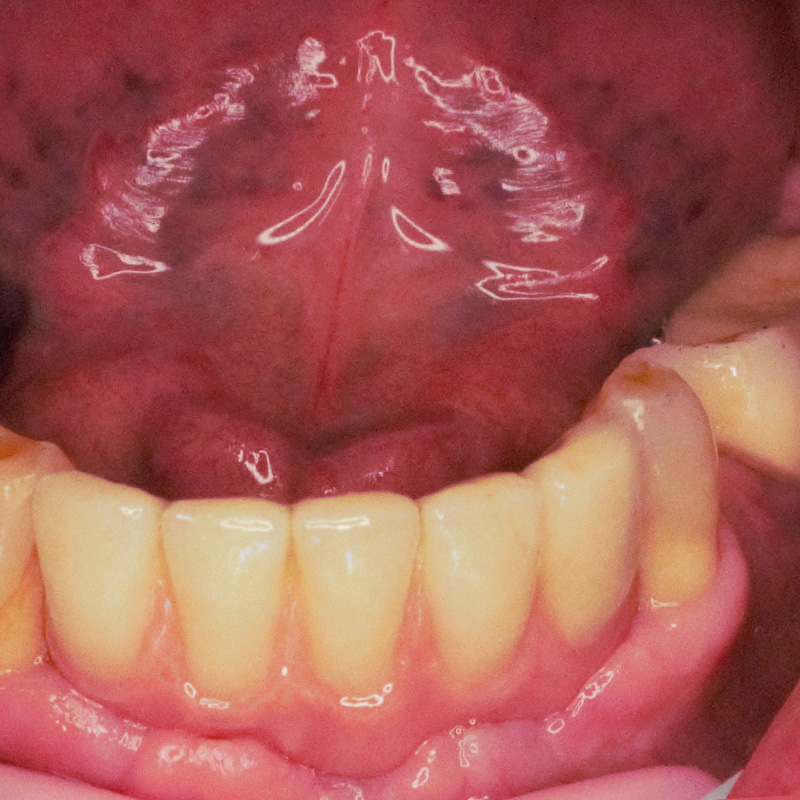

Имплантация зубов верхней челюсти по методу «all-on-6» с одномоментной установкой условно-съёмного протезаСмотреть работуСрок лечения:5 визитовСумма лечения:304 000 руб.